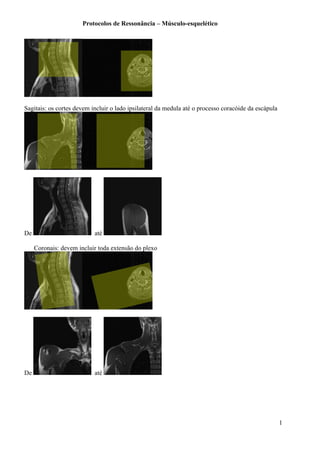

Sagitais: os cortes devem incluir o lado ipsilateral da medula até o processo coracóide da escápula

Coronais: devem incluir toda extensão do plexo